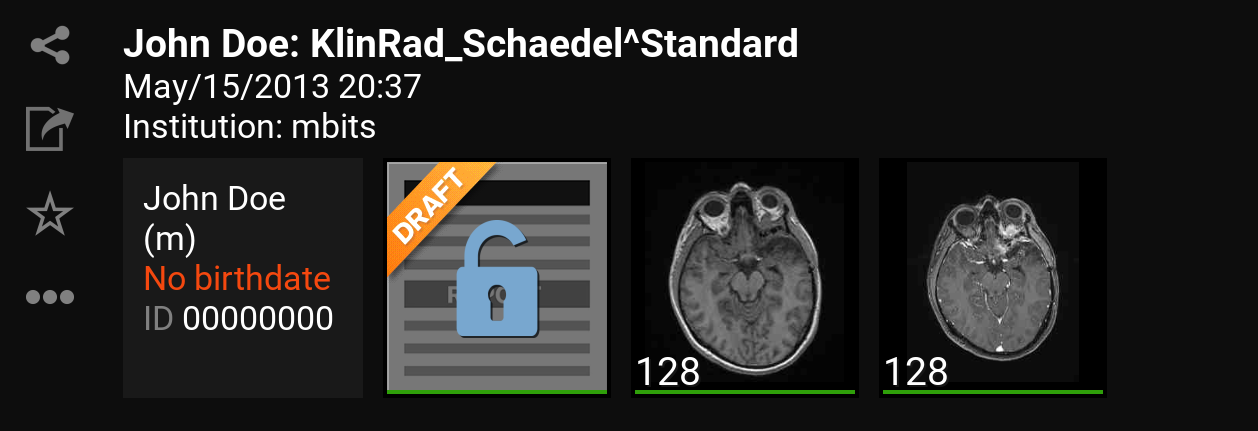

9.1. Inbox

Nach dem Einloggen öffnet sich die „Inbox“ (Inbox). Über diese können Sie den gewünschten DICOM Datensatz selektieren, der Ihnen über den eingestellten Server zur Verfügung gestellt wurde. Sie sehen hier also alle am mRay-Server vorliegenden Daten, auf die Sie Zugriffsrechte haben.

Hier werden Informationen bzw. auch fehlende Informationen und Metadaten zum Patient angezeigt.

-

Hier sehen Sie eine Übersicht der Serien innerhalb der Studie. Durch Anklicken einer Studie kommen Sie in die Serienauswahl (siehe Serienauswahl). Der grüne Balken unter jedem Vorschaubild zeigt an ob der Datensatz lokal auf Ihr Gerät heruntergeladen und offline verfügbar ist.